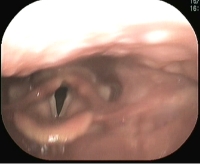

麻痺のために動かなくなった声帯の位置を、なんらかの治療により真ん中に寄せられれば、音声の改善が期待できます。(図 喉頭形成術)

当科では、コラーゲンを声帯の近くに注射することにより声帯の位置を治す喉頭粘膜下異物挿入術と、声帯をとりかこんでいる甲状軟骨の一部に穴をあけて行う、喉頭形成術・披裂軟骨内転術といった手術を行っています。(図 喉頭形成術)

喉頭形成術1型術後7ヵ月 声は大きくなり、楽に話せるようになる